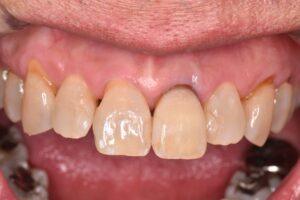

| 備考 | 前歯部の審美障害を主訴に来院されました。 古いコンポジットレジン(プラスチックの詰め物)の辺縁の虫歯や変色によって黒く目立ってしまっている詰め物をダイレクトボンディングという方法でやりかえました。 左上1番の神経を取った歯が茶色に変色していたため、再根管治療として精密根管治療を行い、歯の内部からホワイトニングを行うウォーキングブリーチという方法で歯を白くしました。 赤坂さくら歯科クリニックではダイレクトボンディングと精密根管治療時は必ずラバーダム防湿を行なっております。 患者様は喫煙者で着色も気にされていましたが、綺麗に白くなられてとても喜んでおられました。 続いて奥歯の銀歯のセラミックやジルコニアへのやりかえを希望され、現在治療中です。 |